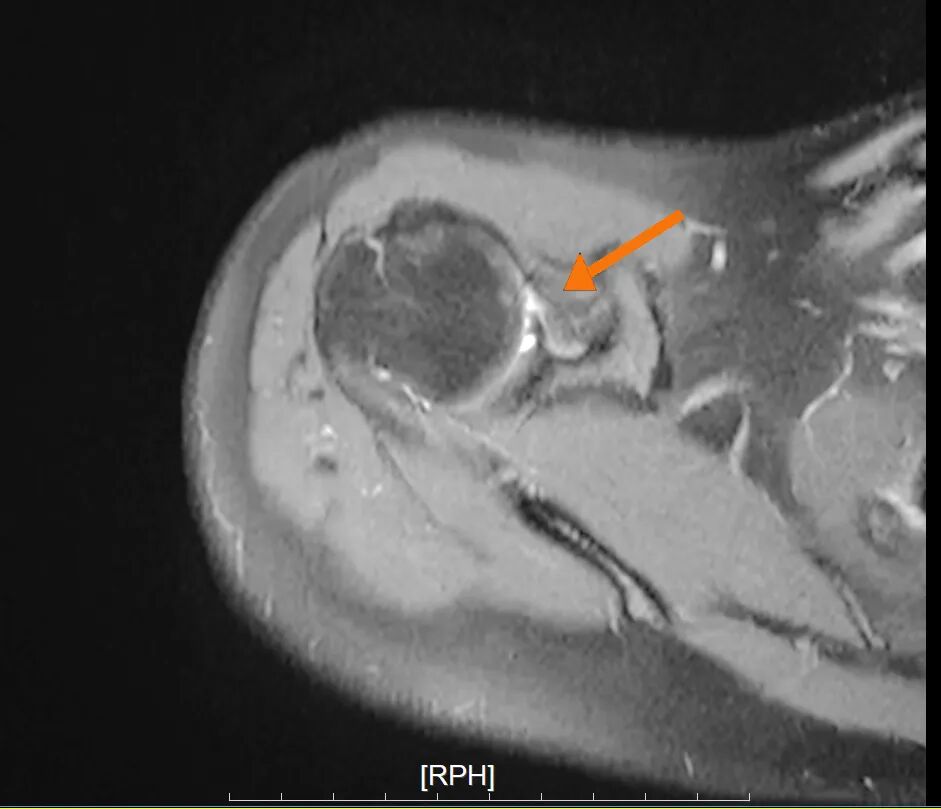

肩关节前盂唇撕裂

肱骨头骨缺损

针对林女士的病情,叶庭均与安亭医院骨科团队制定了关节镜微创手术方案。该手术仅需在肩部开数个不足1厘米的小切口,通过内置摄像头与精密器械精准修复受损部位,具有创伤小、恢复快的优势。手术中,医生发现其肩关节前盂唇存在明显撕裂,并伴有肱骨头骨缺损,随即进行了盂唇修复与关节囊固定术,重建了肩关节稳定性。术后,林女士在骨科团队指导下逐步进行康复训练,肩关节功能恢复顺利,目前已重返日常生活。